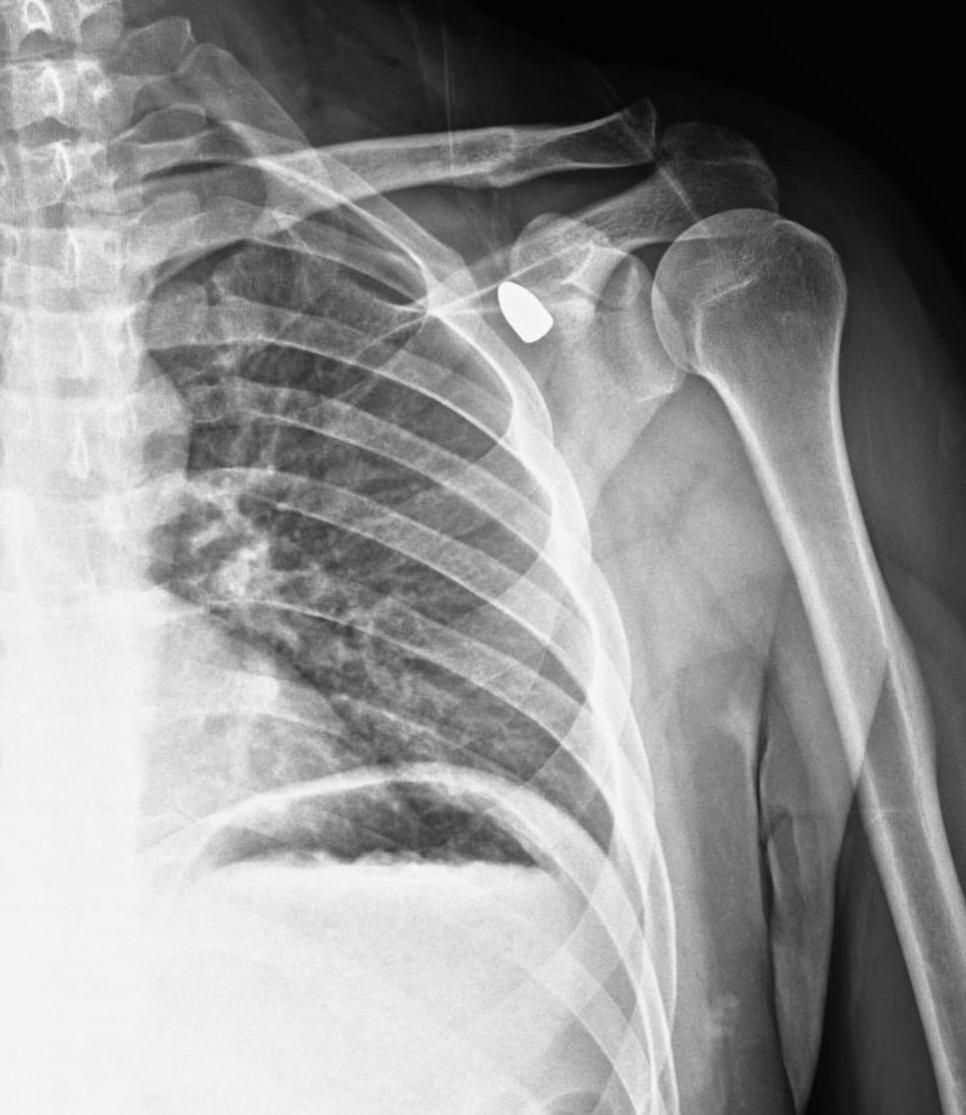

Okul müdürü Celal Şenyiğit, Adsız Mahallesi'ndeki çay ocağında, altı yıl önce omzuna isabet eden yorgun mermiyle yaralandı.

Hareket kaybı riski nedeniyle çıkarılamayan mermi, zamanla Şenyiğit'in koltuk altına ilerledi. Ağrı ve sertlik şikayetiyle Akşehir Devlet Hastanesine başvuran Şenyiğit'in koltuk altındaki kitlenin, omzuna saplanan yorgun mermi olduğu tespit edildi.

Mermi, gerçekleştirilen operasyonla çıkarıldı. Şenyiğit, olayla ilgili şikayetçi olduğunu, çıkarılan merminin incelemeye gönderildiğini söyledi.